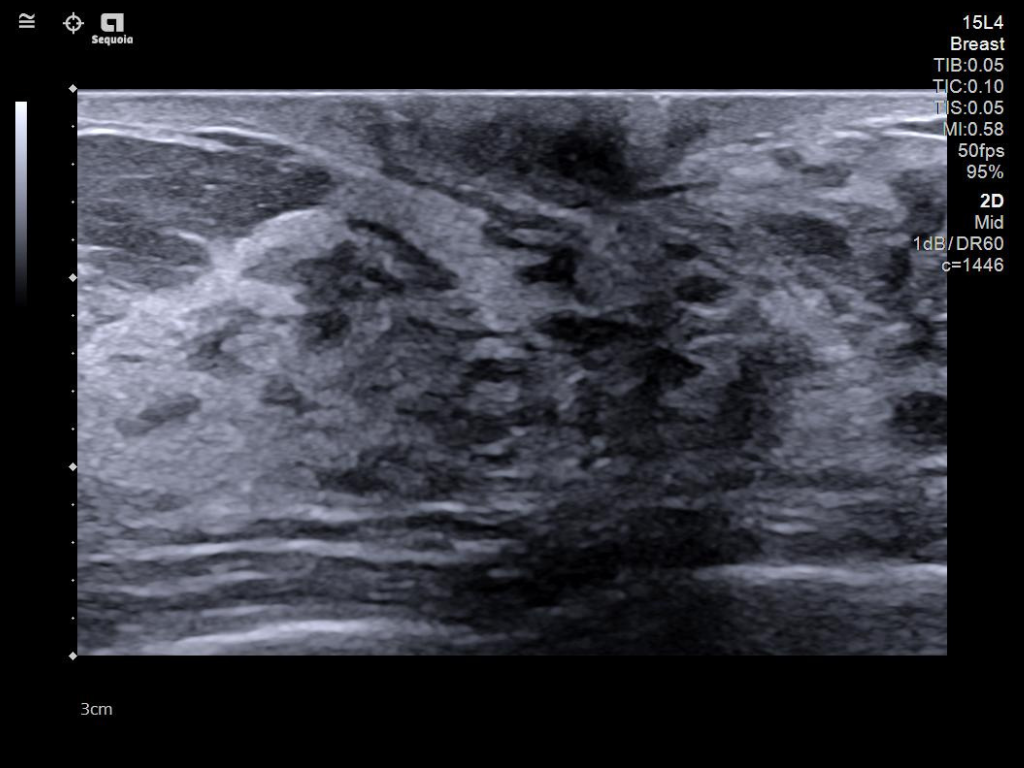

The latest updates on ACUSON Sequoia use the power of groundbreaking AI for abdominal cases, includes advanced breast visualization to deliver new levels of image quality confidence, and tackles the toughest challenges in musculoskeletal imaging, all while saving your team from needless strain and pain.

- Next Gen 2D-SWE for greater sensitivity in detection and visualization of malignant breast lesions.